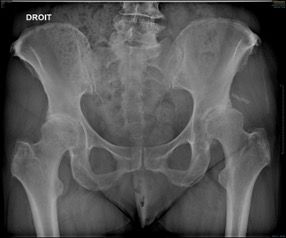

Hips in coxa vara sometimes present a very significant femoral offset which may be prove to be difficult to restore using standard stems. In this case, a varus-tilted or lateralized stem should be used and this will require a very low femoral cut, often with loss of residual femoral offset and a risk of lengthening the lower limb. Positioning a straight cementless stem in varus runs the risk of trajectory error and femoral pain. If a modular neck implant is chosen, the increased lever arm results in significant pressures on the modular neck and neck-head junction with risks that are already known. Finally, even with a cemented stem, positioning it in varus will increase the pressures on the bone-cement interface, with a risk of early loosening. With calcar-guided short stems, the stem will follow the medial cortex of the neck (which will have been cut high), naturally finding a varus tilt and making it possible to reproduce even very significant offsets (Figs 4 and 5).